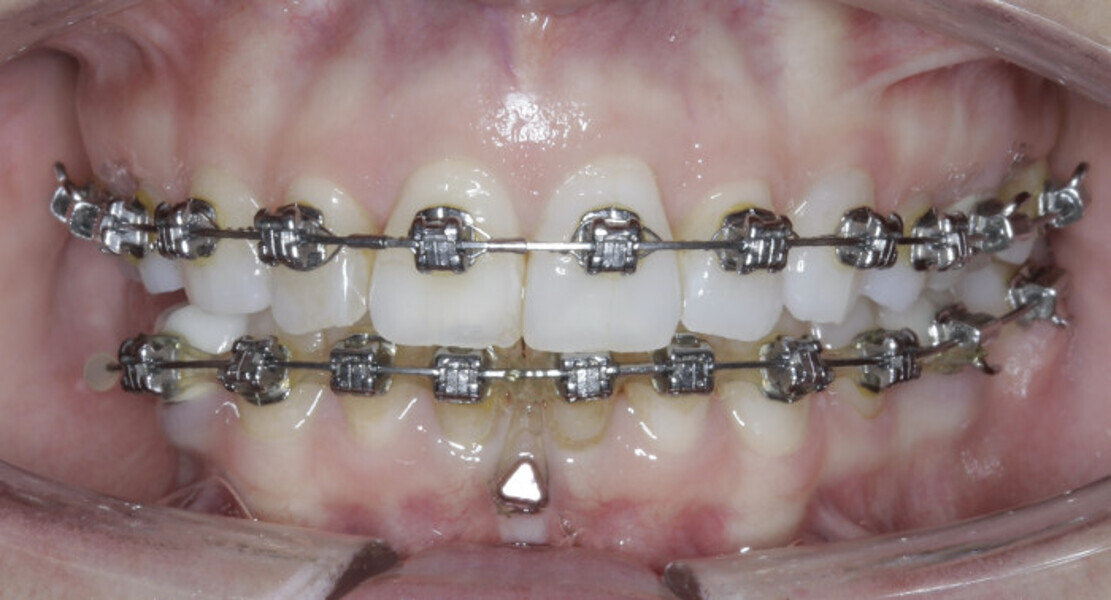

New Age orthodontics and orthopaedics with temporary anchorage devices